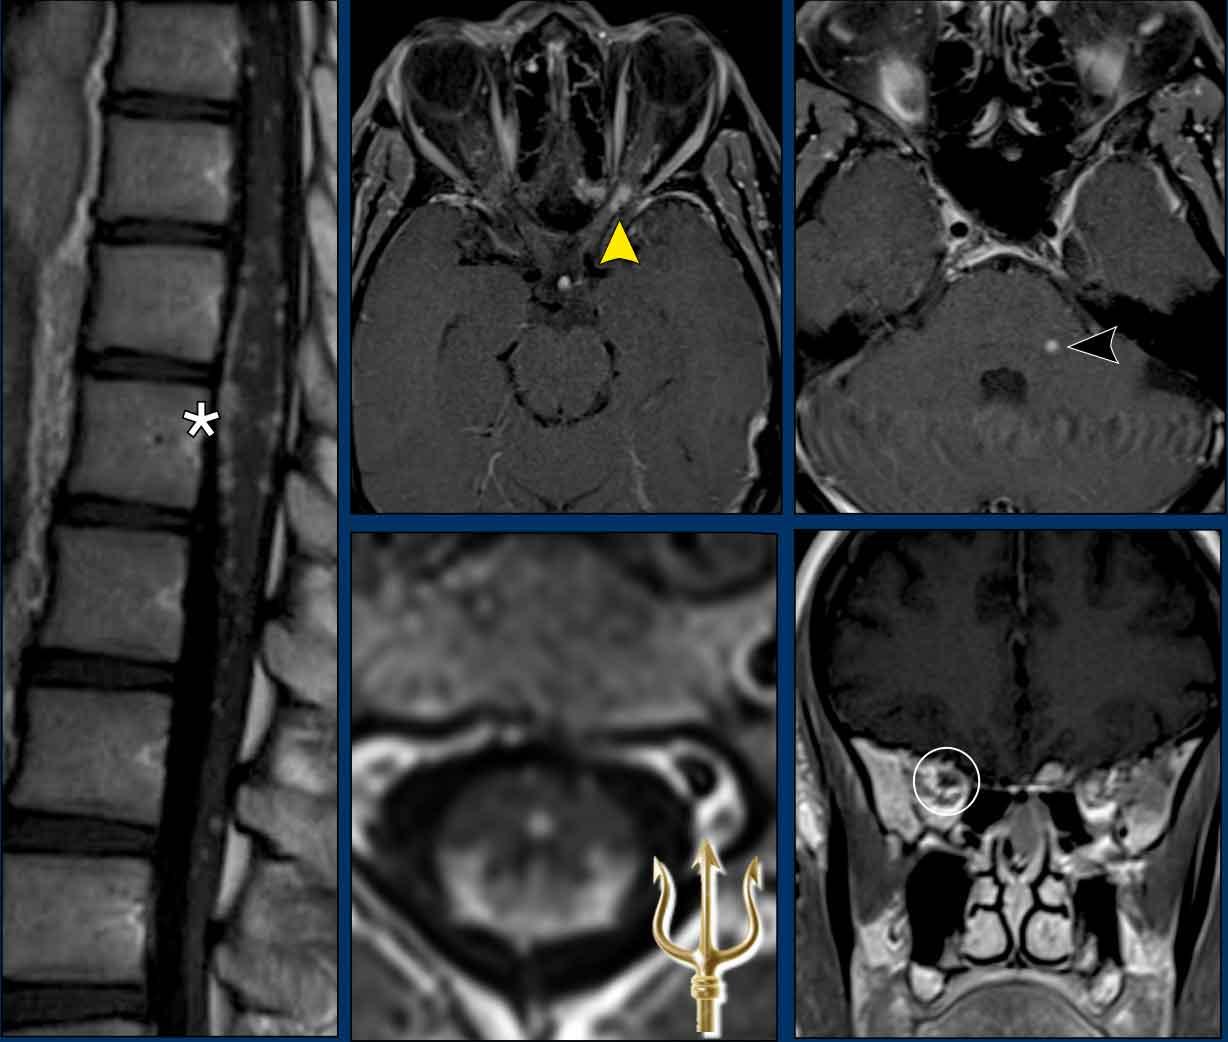

Sarcoidosis thần kinh (Neurosarcoidosis)

Đây là hình ảnh của một nam giới 31 tuổi, nhập viện với đau đầu và giảm cảm giác nửa người.

Hình ảnh

FLAIR cho thấy tín hiệu cao tại các cấu trúc nền sọ, với ngấm thuốc tại và xung quanh các bể nền sọ và bể vallecular.

Các phát hiện này phù hợp với chẩn đoán viêm màng não nền sọ.

Viêm màng não tại nền sọ thường do sarcoidosis, lao, giang mai, hoặc các quá trình u hạt mạn tính độ thấp khác gây ra.

Vì lý do này, CT ngực đã được thực hiện.

Tiếp tục xem các hình ảnh CT…

CT ngực cho thấy các hình ảnh điển hình của sarcoidosis.

Có các nốt nhỏ phân bố dọc theo các khe liên thùy theo kiểu phân bố quanh bạch huyết và hạch rốn phổi to.

Sarcoidosis có thể biểu hiện với nhiều dạng thần kinh và hình ảnh học khác nhau.

Các triệu chứng thần kinh sọ là hệ quả của viêm màng não nền sọ.

Trong hầu hết các trường hợp, cũng có các bất thường trên hình ảnh ngực.

Bệnh nhân này có nhiều nốt màng não mềm.

Các nốt này tăng tín hiệu sau tiêm thuốc tương phản từ và có tín hiệu tương đối thấp trên chuỗi xung T2W, phù hợp với các nốt u hạt.

Đây được xác định là sarcoidosis thần kinh.

Sarcoidosis thần kinh cột sống điển hình có thể biểu hiện với dấu hiệu ‘đinh ba’ (trident sign), trong đó có ngấm thuốc của màng não mềm, chất trắng ngoại vi (*) và ống trung tâm tủy sống.

Ở bệnh nhân này còn có ngấm thuốc của nhân thần kinh sinh ba (đầu mũi tên đen), màng cứng và cả hai dây thần kinh thị giác.

Ngấm thuốc quanh dây thần kinh thị giác trái được thấy rõ nhất trên hình ảnh mặt cắt ngang (đầu mũi tên vàng), trong khi ngấm thuốc bên phải được thấy rõ nhất trên hình ảnh mặt phẳng đứng ngang (vòng tròn trắng).

Trong trường hợp minh họa này, có tín hiệu cao dọc theo các bể nền sọ trên hình ảnh FLAIR và ngấm thuốc màng não mềm dọc theo bể ambiens và vùng tegmentum.

Lưu ý các ổ ngấm thuốc nhỏ ở hồi hải mã phải và thùy chẩm trái.

Đây hóa ra là viêm màng não lao.